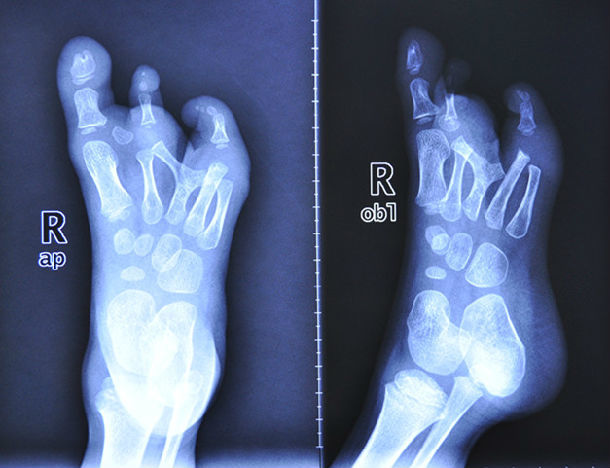

36岁双足拇外翻畸形矫正手术一例

图片尺寸4262x5198